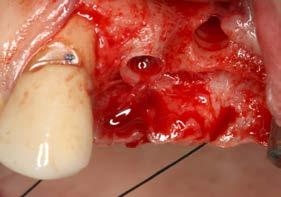

Issuu converts static files into: digital portfolios, online yearbooks, online catalogs, digital photo albums and more. Sign up and create your flipbook.